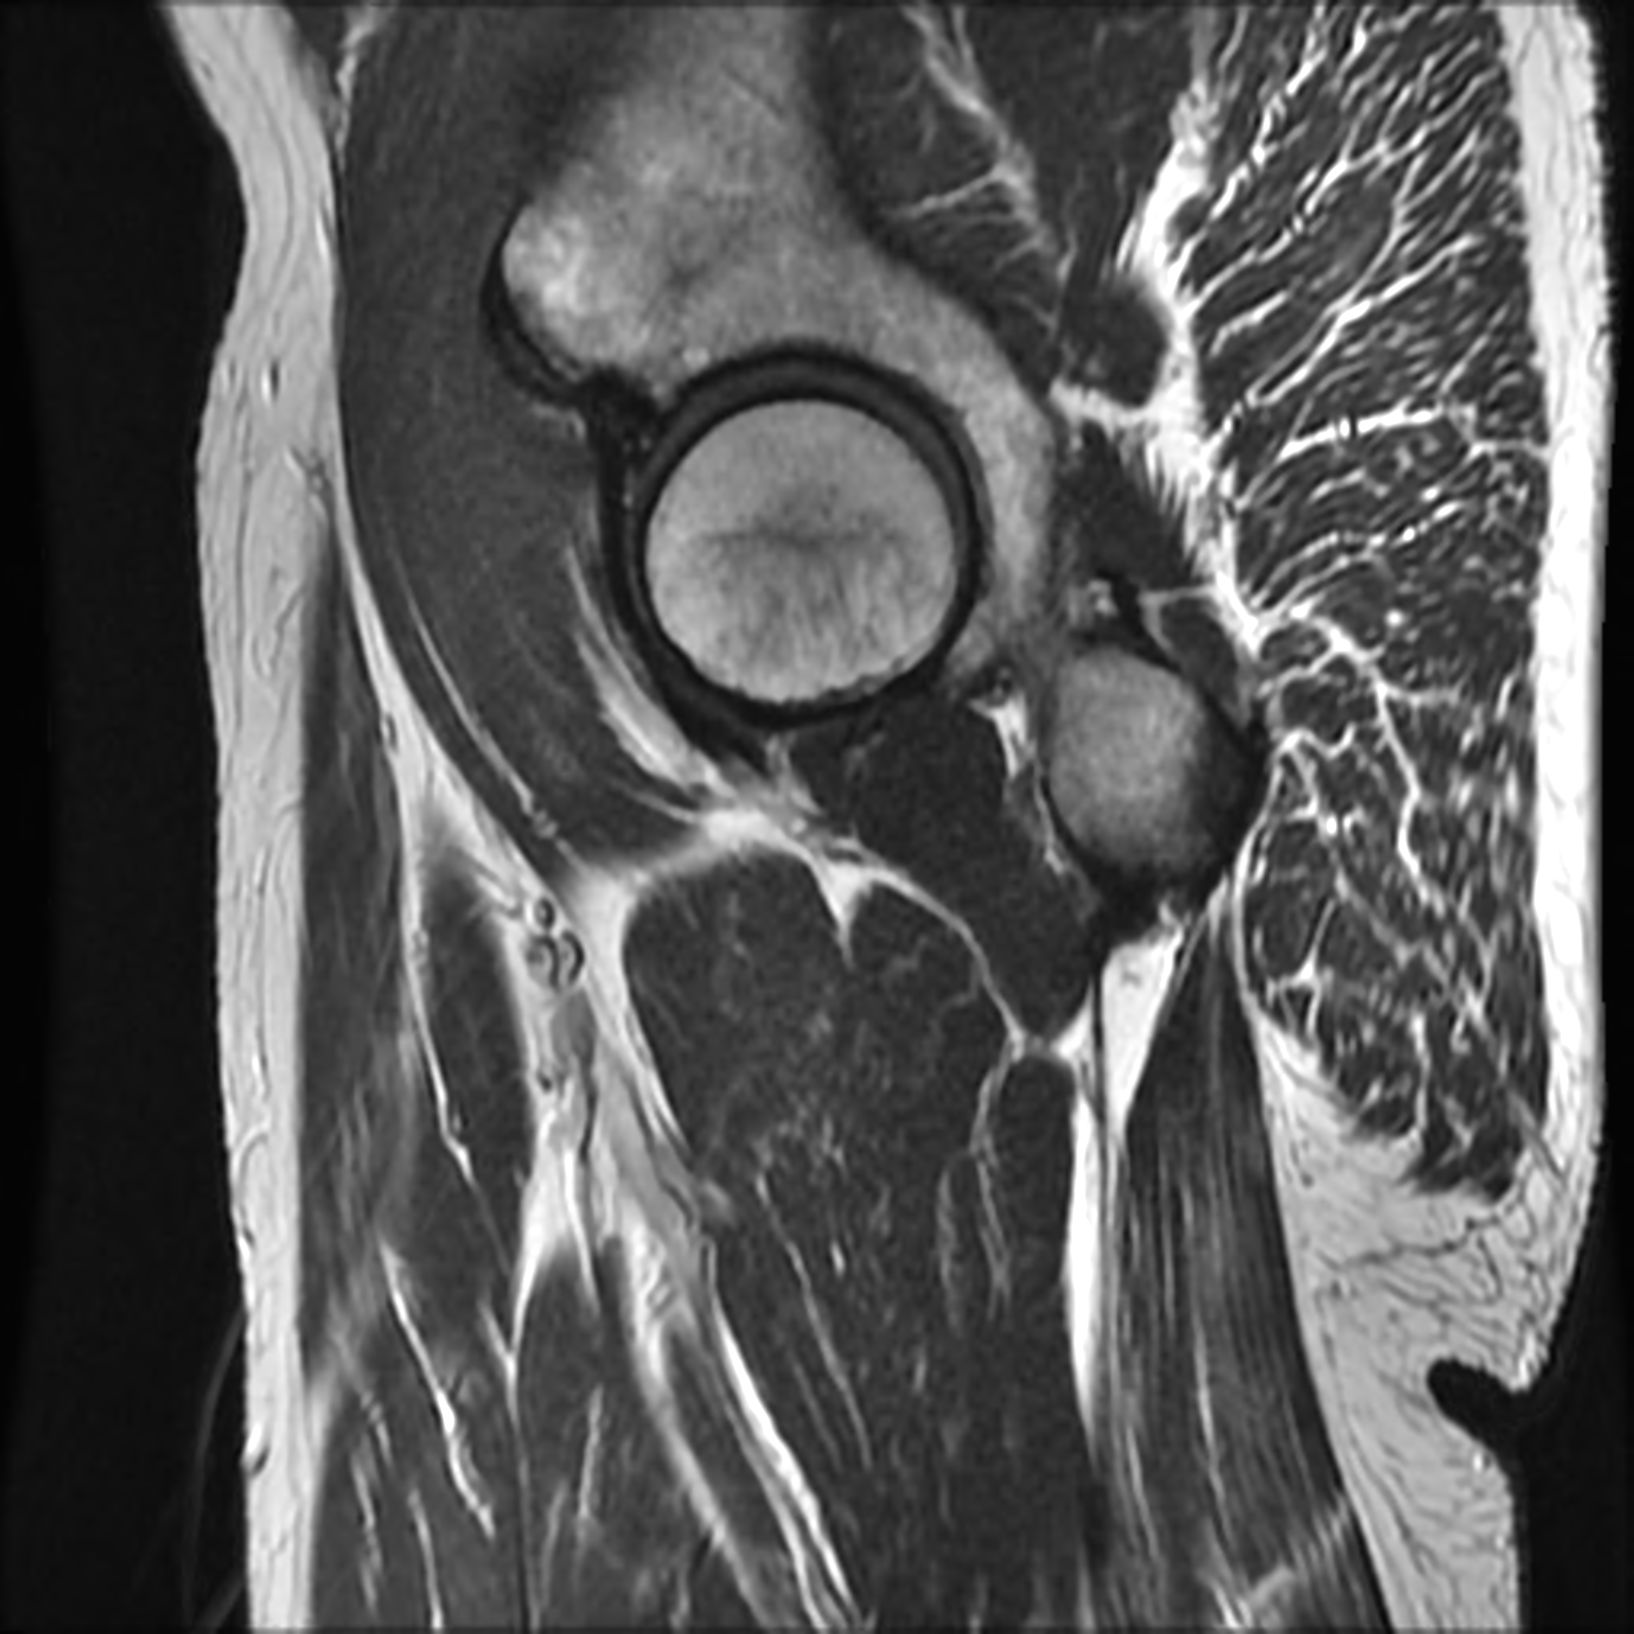

QU’EST CE QUE L’IRM ?

Il s’agit d’un examen d’imagerie médicale qui utilise un champ magnétique pour visualiser les parties du corps humain.

QUELLES SONT LES INDICATIONS DE L’IRM ?

Cet examen permet à votre médecin d’avancer dans sa démarche diagnostique quand l’examen clinique et d’autres examens d’imagerie ne suffisent pas. L'IRM peut être complémentaire des autres modalités d’imagerie que sont l’échographie, le scanner, la scintigraphie,...